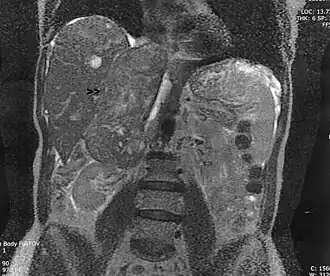

| Leiomiossarcoma em uma veia andrenal (seta), que cresceu do rim até ao coração. Vista coronal de uma Ressonância magnética. | |